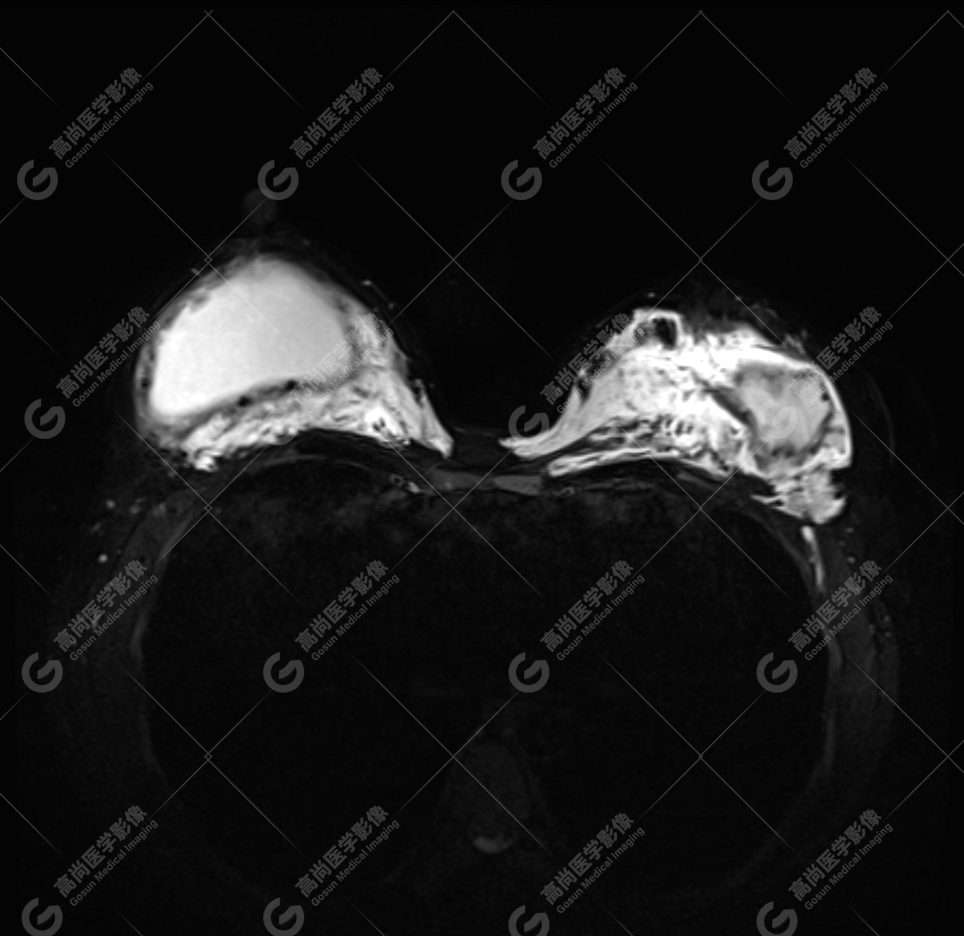

病例 5:乳腺假体植入术后 5 年余

双侧假体外包膜破裂(完全破裂),包膜周围可见内容物渗漏,伴内容物变性、包膜周围炎性反应。